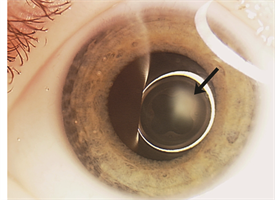

Figure 1.

PFVS falls into the group of ocular diseases in infancy characterized by a white pupil—a result of the abnormal tissue behind the lens (Figure 1)—termed “leukocoria.” While the findings of PFVS are typically restricted to the eyes, other conditions with the findings of leukocoria may be life threatening.